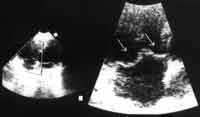

Проведено комплексное клинико-инструментальное обследование 52 детей с идиопатическим ПТК в возрасте от 9 до 12 лет. Обследование детей проводилось в детском кардиоревматологическом отделении МОДКБ. У детей исключались все вероятные заболевания способствующие развитию вторичных ПТК: ревматизм, миокардит, кардиомиопатии, вожденные и приобретенные пороки сердца, заболевания соединительной ткани и др. Критерием отбора детей являлись результаты допплероэхокардиографии (Д-Эхо-КГ) с подтверждением диагноза ПТК. Критерием ПТК было систолическое смещение створок ТК в правое предсердие не менее чем на 3 мм за линию (плоскость) фиброзного кольца ТК (Рисунок).

Рисунок. Сонограмма ребенка с ПТК в апикальной четырехкамерной позиции. Режим увеличения ZOOM. Стрелками отмечены передняя и септальная створки ТК. В большей степени (на 4 мм.) пролабирует передняя створка (левая стрелка).

Для диагностики ПТК наиболее оптимально получение ультразвукового изображения сердца в реальном масштабе времени из апикальной четырехкамерной позиции.